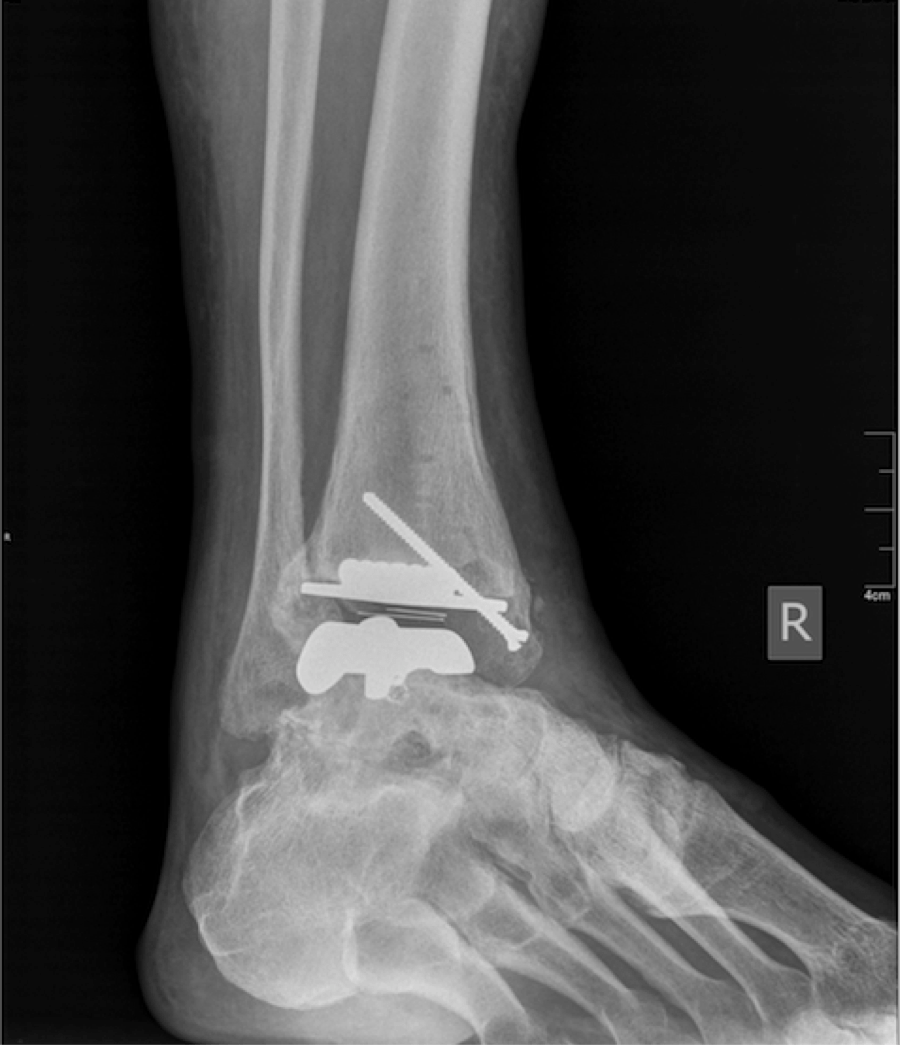

From www.hmpgloballearningnetwork.com

Current Insights On Total Ankle Replacement With Concurrent Endoscopic Gastrocnemius Recession Endoscopic Gastrocnemius Recession Procedure Although traditionally performed as an open procedure, the recession of gastrocnemius fascia can be performed endoscopically through a. What is a gastrocnemius recession? There exists strong evidence to support the use of this procedure in pediatric patients suffering from cerebral palsy, and increasingly enthusiastic. This outpatient procedure is used in the correction of conditions such as flatfoot, chronic achilles tendonitis,. Endoscopic Gastrocnemius Recession Procedure.